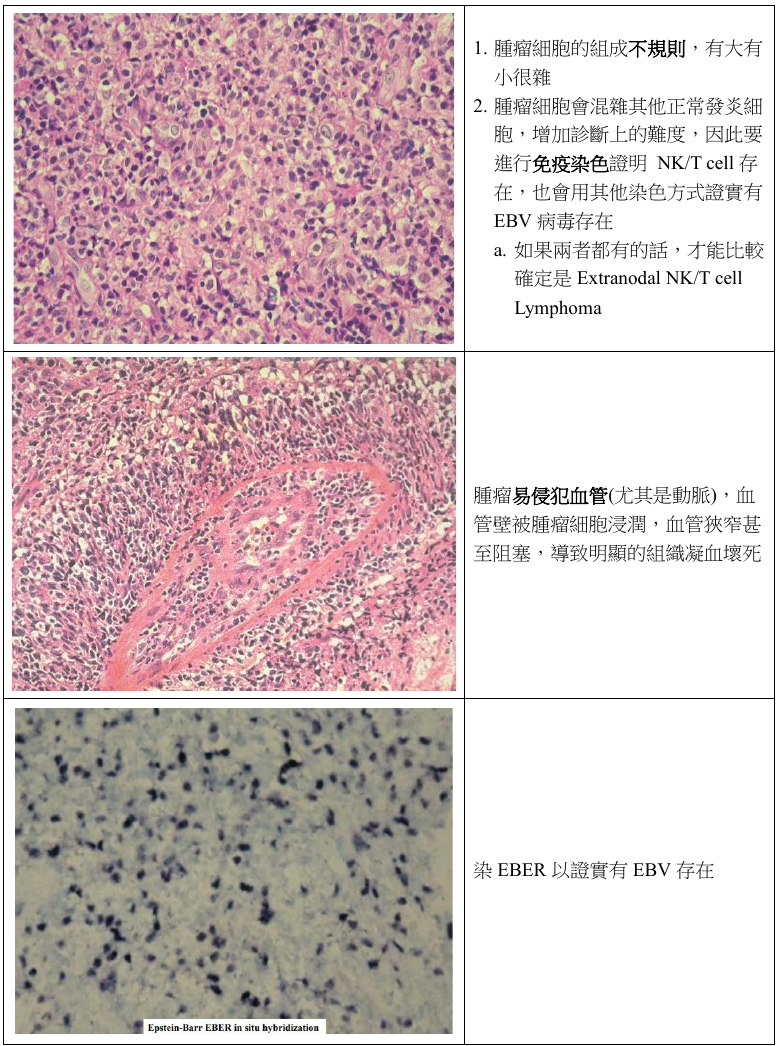

Extranodal NK/T Cell Lymphoma

- EBV related (100%)

- 淋巴結之外的 NK/T cell 所發展出來的

- 長在鼻中線

- 圍著血管長,侵犯血管 (尤其是動脈)

- 造成大區域缺血壞死

- 侵犯性強,化學治療不敏感 → 預後不佳,大部分病歷都在診斷後三年內過世